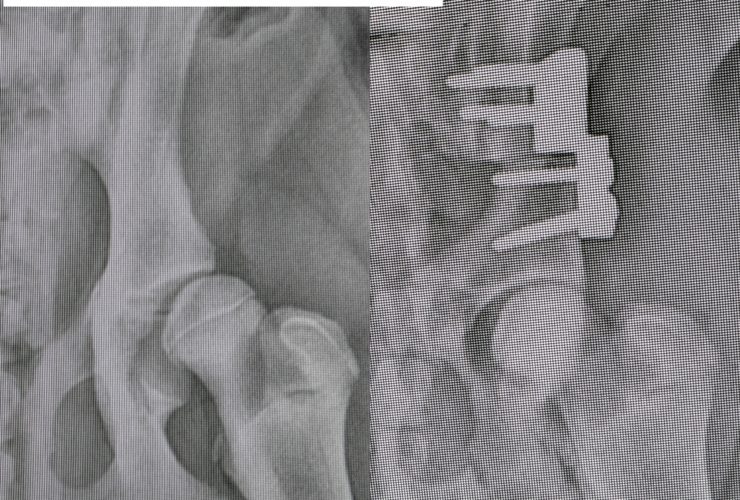

Osteotomia 2.5 de Cadera

La displasia de cadera, por decirlo de forma sencilla y corta, es una enfermedad hereditaria por la que las caderas de los perros no se desarrollan como deberían y acaban teniendo dolor y artrosis. Un día hablaremos de porque se produce y razas predispuestas y demás, hoy me quiero centrar en las opciones quirúrgicas de